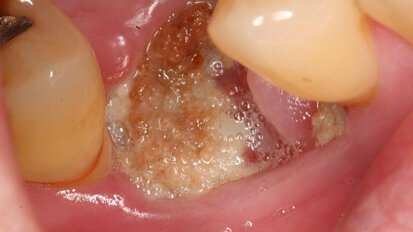

Researchers link amoeba to severe periodontitis

BERLIN, Germany: For the first time, researchers from Charité—Universitätsmedizin Berlin have shown that the amoeba Entamoeba gingivalis, commonly found...